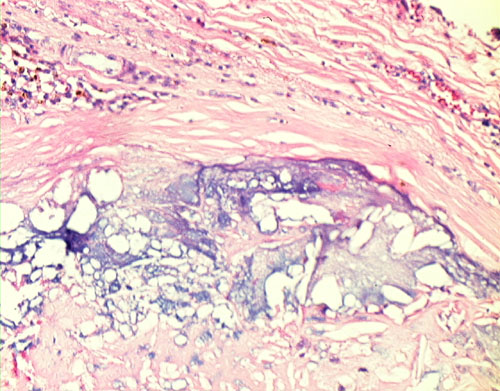

56. Coronary Atherosclerosis, Thrombosis